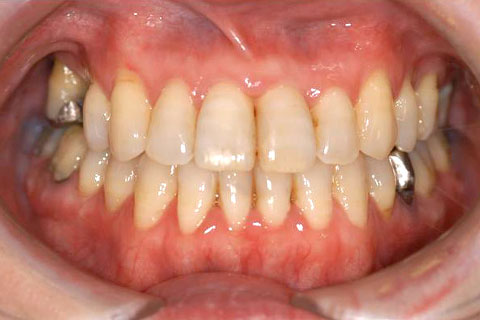

下あごが上あごより突出しているか、上あごが下あごより後退している状態で、咬み合わせが逆になっているので反対咬合ともいいます。お子様の場合、受け口(反対咬合)を放置していると、成長期において下あごが過大に成長し悪化しますので、出来る限り早い時期に治療することをおすすめします。受け口(反対咬合)は見た目の問題だけでなく顎の動きを制限し、将来的に顎の痛み(顎関節症)を引き起こす場合があります。また、お子様の場合は、正常な上顎の成長を阻害する可能性があります。

受け口(反対咬合)の症例

症例一覧